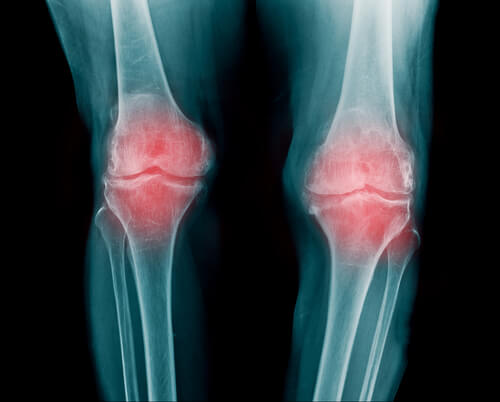

- Rheumatoid arthritis is inflammation of the joint. It may affect multiple different joints. Generally, it affects the fingers, arms, and knees.

- People with rheumatoid arthritis have reduced mobility. After the tingling, worse pain begins.

- It happens when calcium deposits accumulate in the joint. Then come the tingling joints and weakened cartilage, which gradually breaks down and causes pain to get worse.

- We see it most often in the wrists, fingers, and knees. However, it may affect other joints as well. This illness is related to osteoarthritis and thyroid disorders.